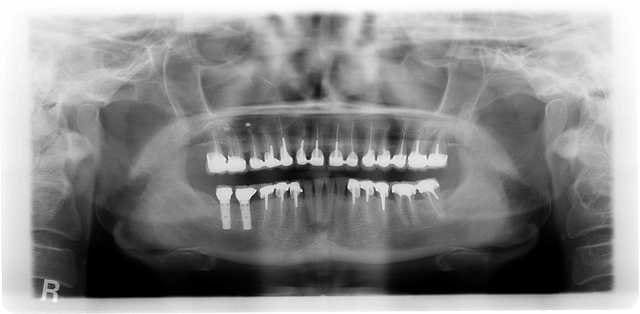

radio en 2011

ça va non ?

012011 wsypdn - Eugenol